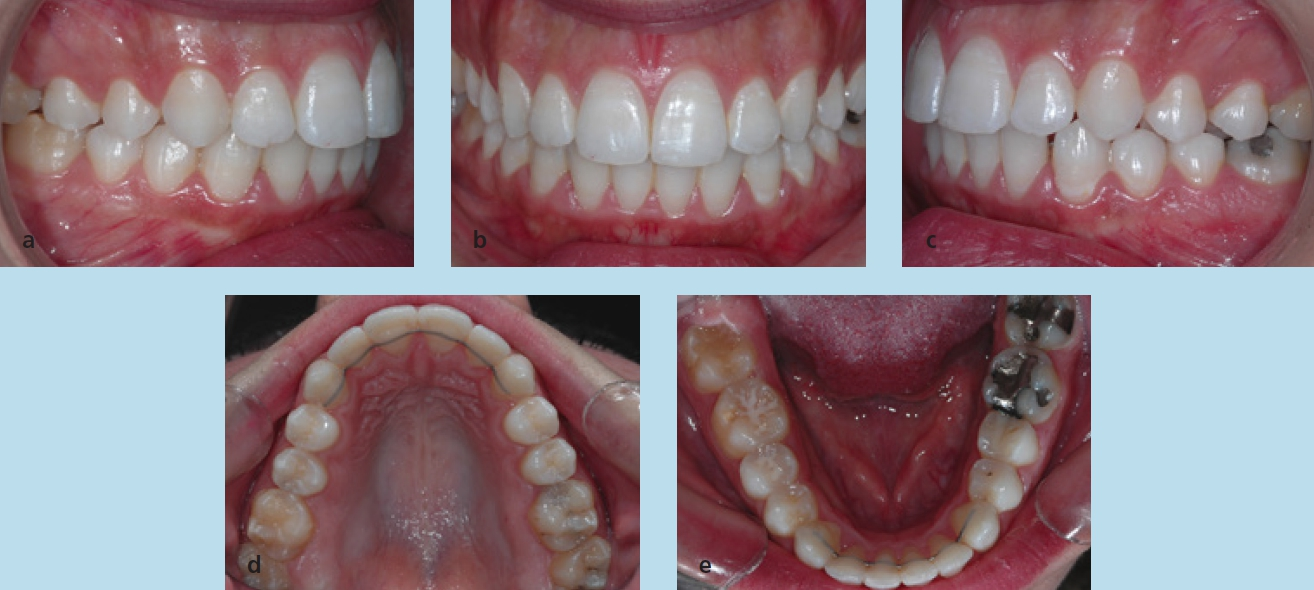

Die Patientin stellte sich im Alter von 23 Jahren zu einer kieferorthopädischen Beratung vor. Sie störten die Engstände im Unterkieferzahnbogen. Die extraoralen Aufnahmen zeigen ein schönes, harmonisches, leicht konvexes Profil, das nach den Grundregeln der Ästhetik nicht verändert werden darf (Abb. 18a bis c). Die intraoralen Aufnahmen zeigten zu Behandlungsbeginn eine Angle-Klasse-I-Okklusion, Tendenz zu Klasse III rechts und Klasse I links. Auf der Frontalaufnahme ist die knappe sagittale und vertikale Frontzahnstufe zu sehen (Abb. 19a bis c). Im Rahmen der Modellanalyse konnte eine harmonische Breitenrelation beider Zahnbögen im Bereich der Molaren und Prämolaren ermittelt werden, im Oberkiefer waren die Platzverhältnisse ausgeglichen. Im Unterkiefer lag ein Engstand von insgesamt 5 mm vor, wobei sich die Engstände auf die Frontzahnregion konzentrierten (Abb. 19d und e). Das angefertigte OPG (Abb. 20) zeigte, dass alle Zähne vorhanden und die Zähne 38 und 48 retiniert und verlagert waren. Im Seitenzahngebiet war eine konservierende Versorgung zu verzeichnen. Die parodontale Situation war röntgenologisch sowie klinisch unauffällig und die Knochenverhältnisse ließen eine orthodontische Behandlung zu. Die Fernröntgenaufnahme (Abb. 21) zeigte keine skelettalen Auffälligkeiten. Die Oberkieferfront stand nahezu achsengerecht, die Unterkieferfront war nach labial gekippt (Tab. 3).